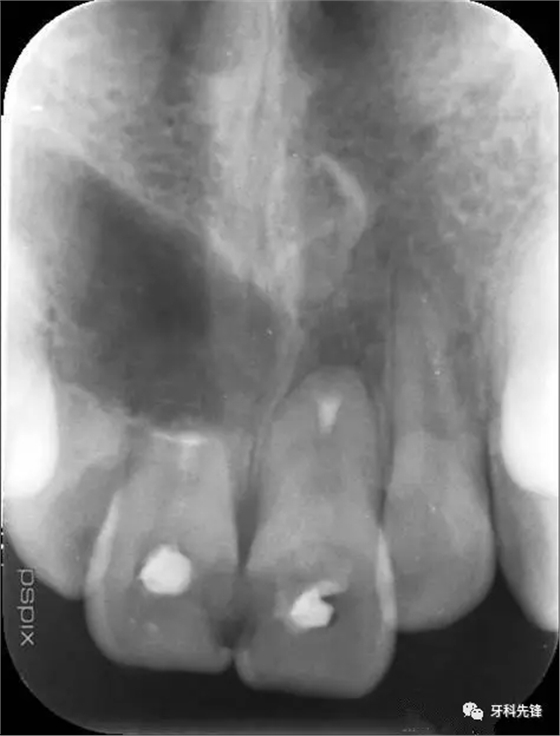

圖1.術前的根尖片影像:12、11根尖2/3壓迫吸收、11、21根管內(nèi)各有一牙膠尖。

圖15.術后11、21根尖片影像、MTA封閉11、21根尖。12暫時不處理,觀察。